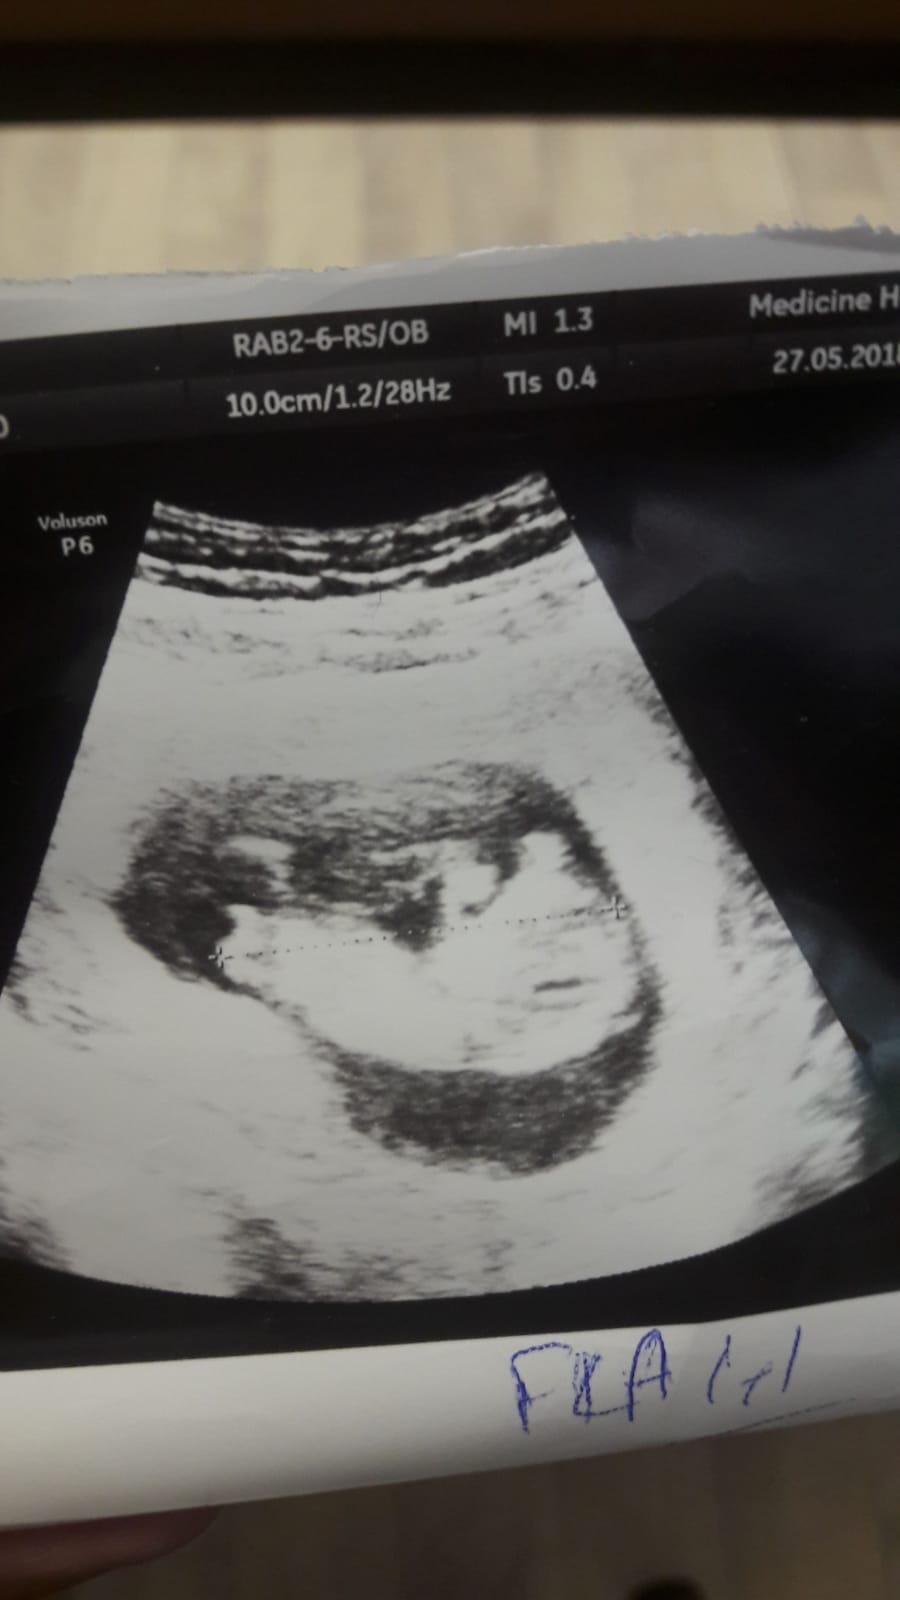

Merhaba, benim fotoğrafımı da yorumlayabilir misiniz rica etsem..

Merhaba, görseliniz pek net değil bebeğinizin cinsiyeti kıza benziyor .Hatırlatma yapalım bebeğinizin cinsiyetini net olarak 17-18-20. haftada öğrenebilirsiniz. Öncesi yapılan tahminler yanıltabiliyor.